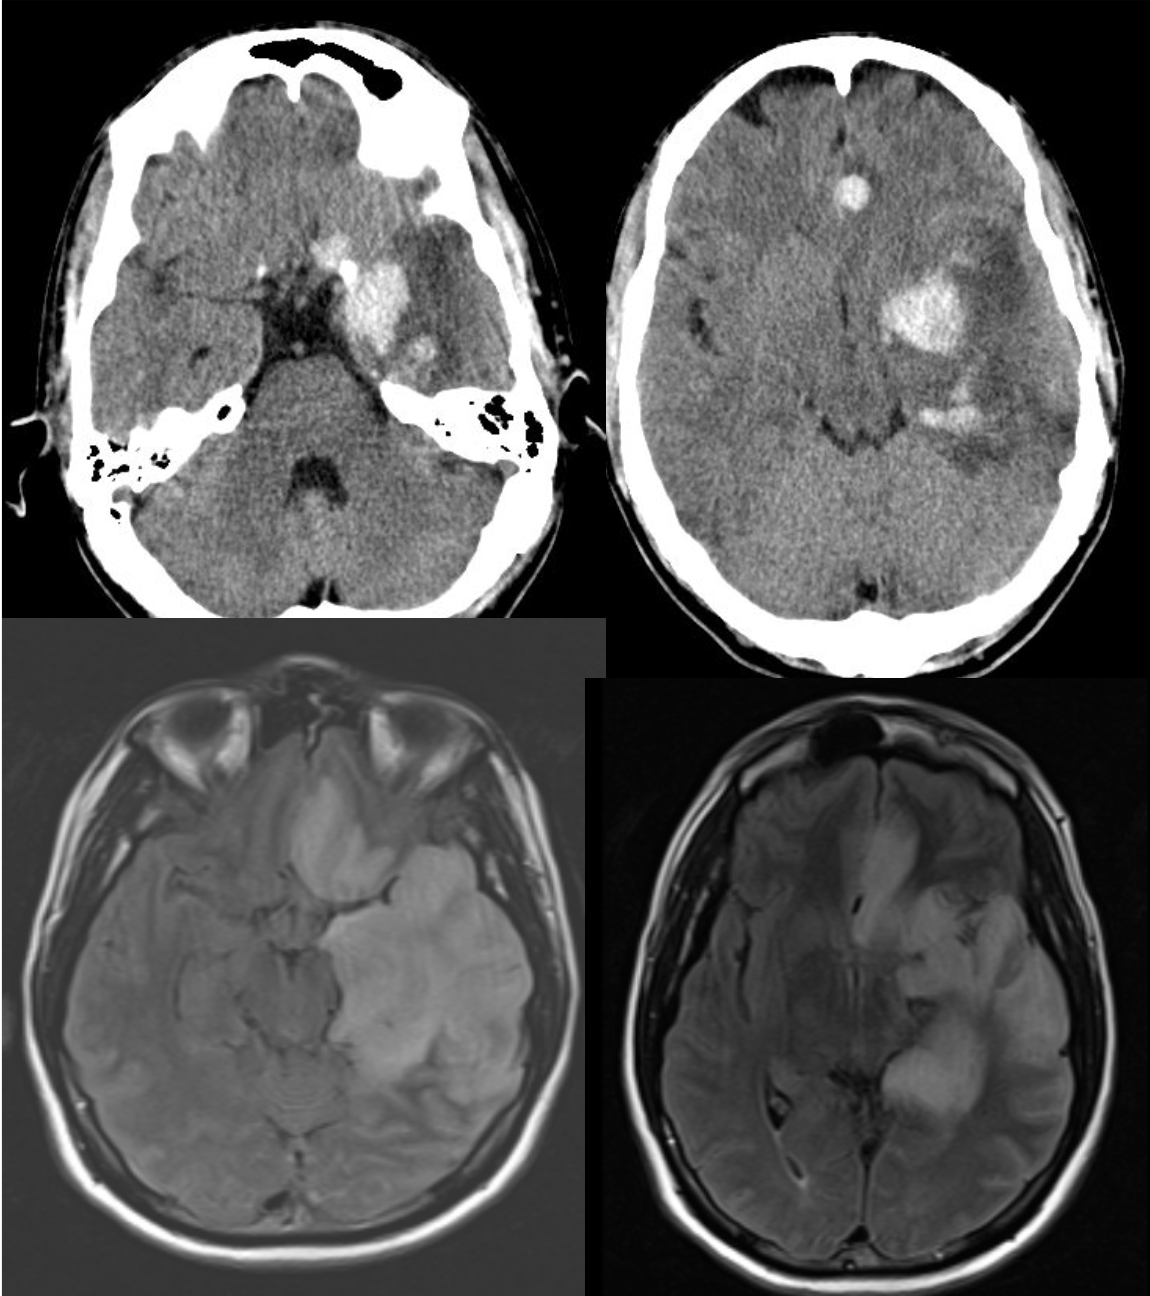

HIV patient with left-sided weakness.

Toxoplasmosis

Imaging